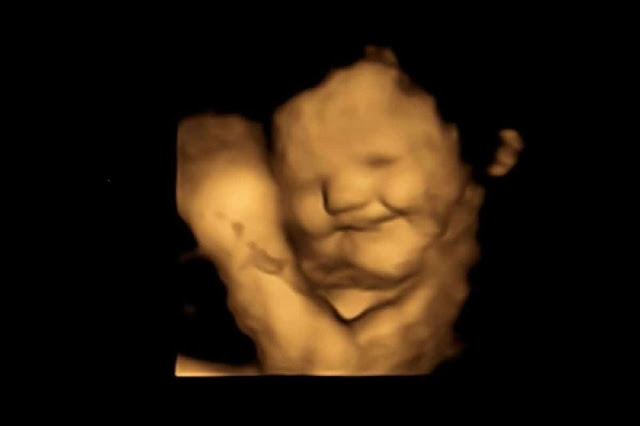

El equipo de investigación reunió a 100 mujeres de entre 18 y 40 años que estaban embarazadas de 32 o 36 semanas. Las madres recibieron una sola cápsula que contenía unos 400 mg de zanahoria o 400 mg de col rizada unos 20 minutos antes de cada exploración. A continuación, los investigadores fabricaron un ultrasonido 4D. Una ecografía en 4D permite ver claramente la cara de los bebés por nacer. Poco después de tomar la cápsula, se estudiaron las caras de los fetos para evaluar su reacción a los sabores.

Los investigadores llegaron a un curioso descubrimiento. De hecho, incluso una pequeña cantidad de zanahoria o col rizada parece provocar una reacción en el feto. Se prefiere claramente la zanahoria. La zanahoria, por ejemplo, hizo sonreír a los fetos, mientras que tras probar la col rizada pusieron mala cara.

Izquierda: ecografía en 4D de un bebé no nacido que sonríe tras probar una zanahoria. Derecha: El mismo feto pone mala cara tras probar la col rizada. Imagen: Estudio FETAP (Fetal Taste Preferences), Fetal and Neonatal Research Lab, Durham University

"Fue realmente fantástico ver la reacción de los bebés no nacidos a los sabores de la col rizada y la zanahoria y compartir esos momentos con sus padres", recuerda Ustun.